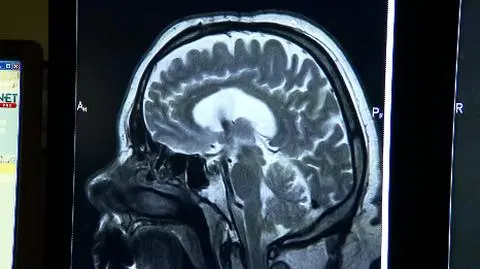

Naukowcy w ramach tego projektu chcą stowrzyć superkomputer, który ma być jednocześnie najwierniejszym modelem mózgu jaki kiedykolwiek zbudowano. Zadanie ambitne, nic dziwnego, że zaplanowane na dekadę i angażujące ponad 80 ośrodków naukowo-badawczych w całej Europie, w tym w Polsce. Dr Piotr Bogorodzki będzie członkiem grupy odpowiedzialnej za skatalogowanie badań rezonansu magnetycznego. Co dzień robi się ich w Europie kilkadziesiąt tysięcy, ale nikt ich nie analizuje, zebrane w bazę mogłyby posłużyć jako materiał do ważnych obserwacji. - Wykorzystując najnowsze techniki komputerowego przetwarzania, czyli poszukiwania jakis wzorców i na tej podstawie będziemy w stanie wyodrębnić tzw. biomarkery, charakterystyczne zmiany - mówi polski koordynator "HBP".